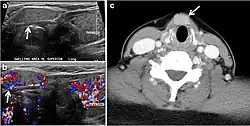

Fig. 13. A 27-year-old female patient known to have goiter. a, b Axial and sagittal enhanced CT scan images of the neck demonstrate a heterogeneously enhancing, enlarged thyroid gland with scattered calcifications (white arrow), cystic changes, and substantial retro-sternal extension (black asterisks). No lymphadenopathy or substantial airway narrowing.[1] -

Fig. 14. A 19-year-old male patient known to have multi-nodular goiter and FNA, showing underlying Hashimoto's thyroiditis. a, b Sagittal and transverse greyscale and colour Doppler ultrasound of the neck demonstrate a hypoechoic enlarged right thyroid lobe with small hyperechoic regenerative nodules and marked hypervascularity (white arrows). c, d Enhanced axial CT scan images of the neck demonstrate a heterogeneously enhancing and enlarged thyroid gland, left more than right lobe, and the trachea is markedly narrowed.[1] -

Fig. 15. A 33-year-old female patient who presented with neck swelling and pain and was later diagnosed with Hashimoto's thyroiditis. an Axial enhanced CT scan of the neck demonstrates minimal diffuse enlargement of the thyroid gland, especially the isthmus (white arrow). b Transverse greyscale ultrasound of the neck demonstrates heterogeneously enlarged thyroid and thickened isthmus, measuring 8.6 mm.[1]